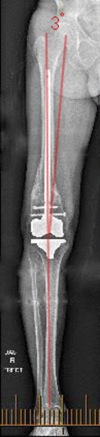

Multiple acceptable options are available for the correction of distal femoral deformity associated with knee arthritis. The treatment modality should be chosen based on the extent of deformity and attention to preservation of the collateral ligaments. Surgical options range from osteotomy alone, arthroplasty with intra-articular correction, or arthroplasty with extra-articular correction. Different implant choices and fixation methods for the osteotomy possess advantages and disadvantages which need to be considered carefully. In addition to discussing principles of management based on current literature, this article includes a case report using a previously undescribed technique using corrective osteotomy, intramedullary nail fixation, and total knee arthroplasty with computer navigation.